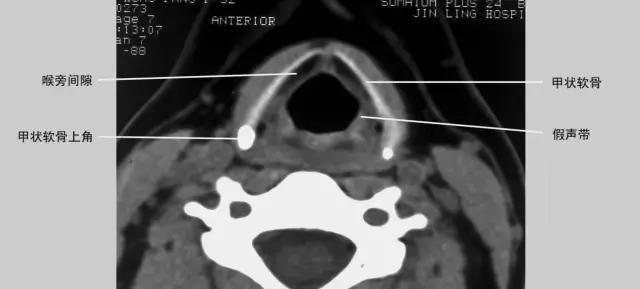

正常喉部CT